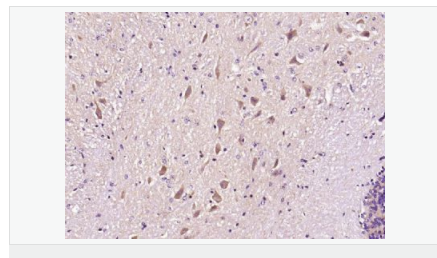

image.png